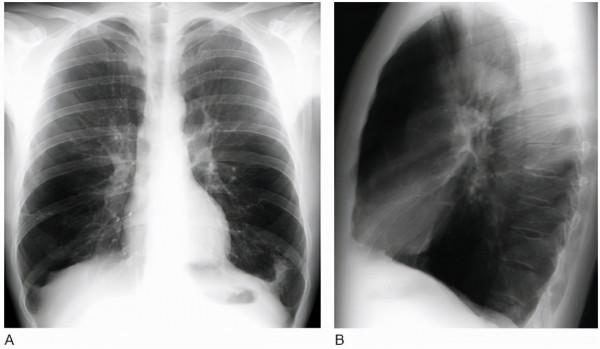

患者肺部紋理增強,常見於生理因素和病理因素兩大類,具體如下:

1、病理性因素:常見於支氣管炎,是由於病毒、細菌、支原體,還有其他的病原體入侵,導致支氣管黏膜出現了充血、水腫以及炎性分泌物滲出的改變,通常肺部的肺門處組織,還有肺部的血管、淋巴管等出現有充血、水腫的狀態,透過拍雙肺的CT、X光片,能夠發現肺部紋理增強。

2、生理性因素:主要常見於部分老年人以及比較肥胖的人群,是生理現象,沒有出現任何的症狀。朋友們聽明白了嗎,如果還是不明白,或者你也看不懂報告的,自己無法判斷的,可以把片子發給我,我來為你解讀。